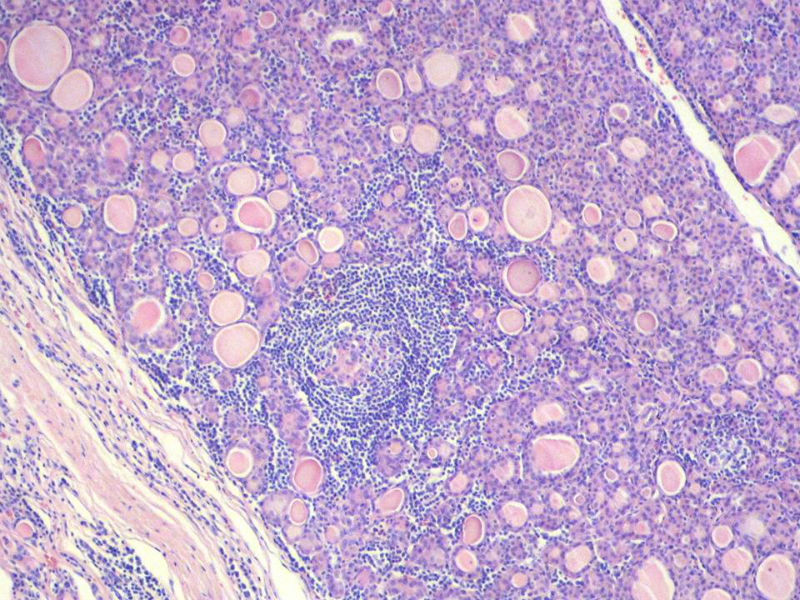

女,60岁,右侧甲状腺肿物两个月,术中见肿块与周围组织无粘连,肉眼,灰红色组织,3X2X2厘米,切面见一直径2.5厘米肿物,包膜完整,灰黄色,质软。

右侧甲状腺肿物图1

名称:图1

具有桥本氏病的大部分特征,有结节形成,此情况有称之为“结节性桥本甲状腺炎”